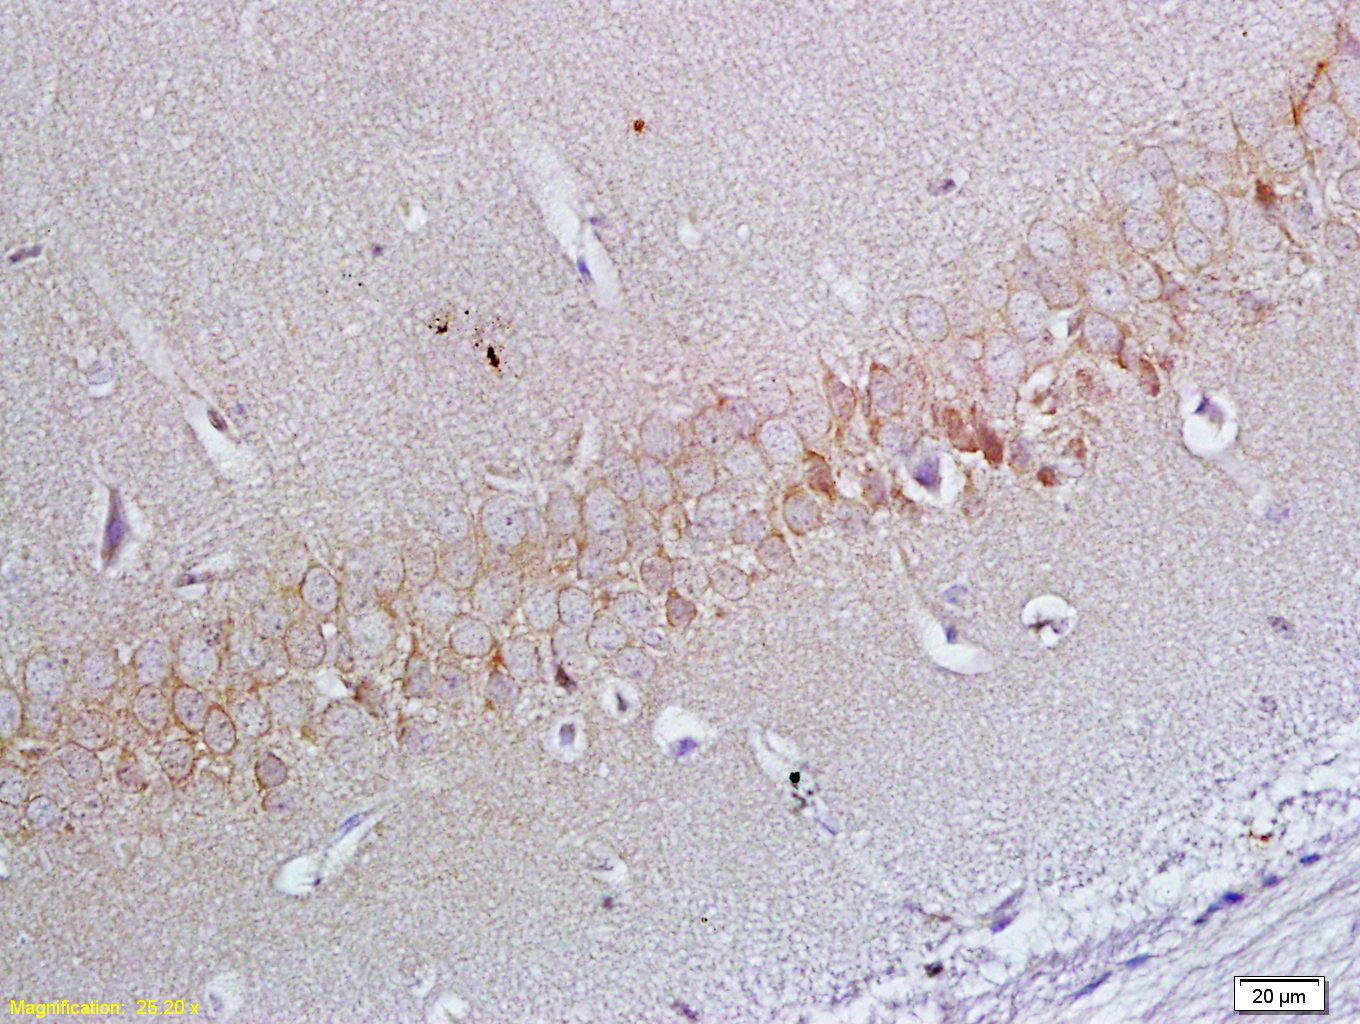

| 英文名称 | ApoER2 Rabbit pAb |

| 中文名称 | 载脂蛋白E2受体抗体 |

| 产品应用 | WB=1:500-2000, IHC-P=1:100-500, IHC-F=1:100-500, IF=1:100-500 Not yet tested in other applications. |

| 交叉反应 | Human, Mouse, Rat (Chicken, Dog, Pig, Cow, Horse, Rabbit) |

Antigen retrieval: citrate buffer ( 0.01M, pH 6.0 ), Boiling bathing for 15min; Block endogenous peroxidase by 3% Hydrogen peroxide for 30min; Blocking buffer (normal goat serum,C-0005) at 37℃ for 20 min;

Incubation: Anti-ApoER2 Polyclonal Antibody, Unconjugated(bs-6651R) 1:200, overnight at 4°C, followed by conjugation to the secondary antibody(SP-0023) and DAB(C-0010) staining